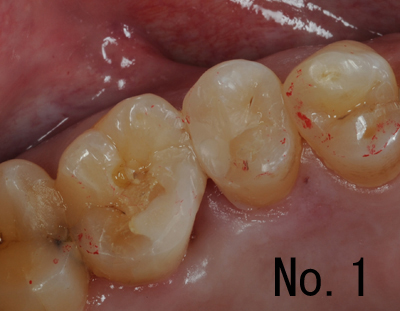

下記の画像は、保険診療であり、直接口腔内で充填処置をしたものです。No.2とNo.3は同一歯で近心のみの修復完了の画像で、途中です。保険での診療が主ですので、写真を撮り忘れて(撮っている時間がないことが多い)しまってることがほとんどです。日常的な治療方法と言えるでしょう。